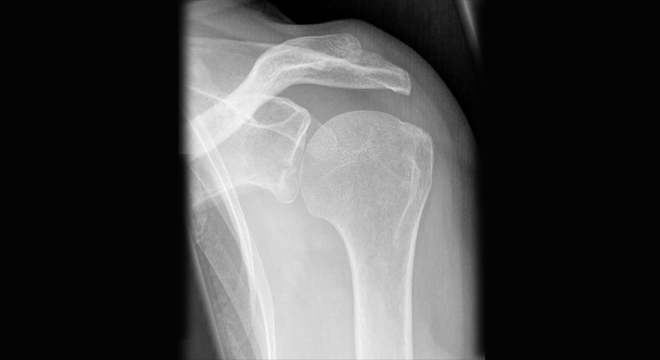

schultergelenkentzündung: Röntgenbild des Schultergelenkes

• Röntgenbilder